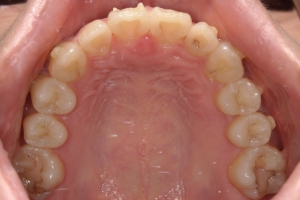

BEFORE

治療前

下の前歯が上あごの歯ぐきに当たるほど噛み合わせが深く、そのことが原因で上顎歯列の正中にすき間(正中離開)が生じていました。部分矯正ですき間を無理やり閉じても、噛み合わせが深いままでは治療後の再発リスクが高くなります。そのため全体矯正で奥歯の噛み合わせを整え、噛み合わせを浅くしつつ前歯を並べました。正中離開は戻りやすい傾向があるので、再発を防ぐため固定式リテーナーを推奨しています。